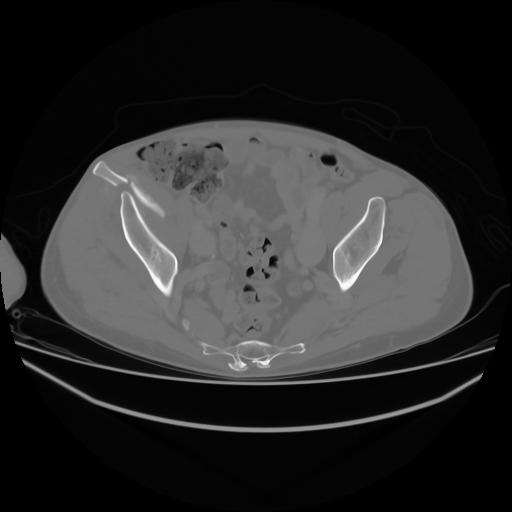

4 CUERPO,CE,Axial,3.0,CUERPO,,